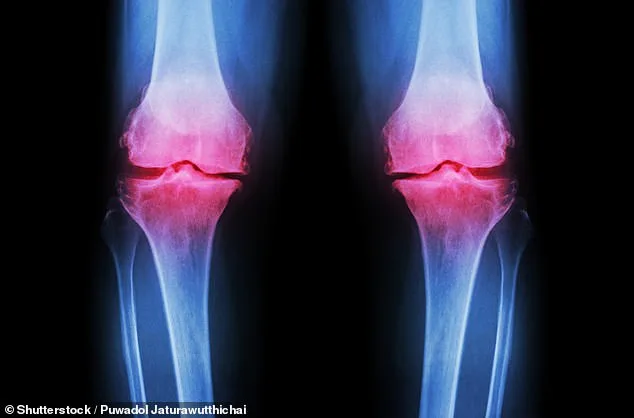

A groundbreaking advancement in medical science may soon offer hope to millions of Americans grappling with osteoarthritis, a condition that affects over 32 million individuals nationwide. Researchers at Columbia University have pioneered a method to grow a fully functional human knee in the lab, a development that could revolutionize treatment for patients suffering from this debilitating disease. The process involves creating a 3D-printed scaffold made of biodegradable material, which is then seeded with bone and cartilage cells. Over the course of approximately one year, these cells regenerate natural tissues, while the scaffold gradually dissolves, leaving behind a complete lab-grown knee. This innovation, still in its early stages, represents a potential permanent solution for osteoarthritis, a condition that currently lacks a cure and relies on pain management or invasive surgical interventions like joint replacement.

Osteoarthritis occurs when the cartilage that cushions joints wears down, leading to chronic pain, stiffness, and reduced mobility. For the 14 million Americans with knee osteoarthritis, existing treatments are often temporary at best. Pain-relief injections provide short-term relief, while joint replacements require lengthy recovery periods and carry significant risks. The Columbia team's prototype, though not yet tested in live human patients, has already been implanted into cadavers to assess its ability to bear weight and support movement. If successful, the next steps involve preclinical trials in large animals, followed by human testing. The researchers emphasize that the living knee could integrate with the body's blood vessels, allowing it to function like a natural joint. However, questions remain about the treatment's scalability and whether it could be adapted for other joints affected by osteoarthritis, such as hips or feet.